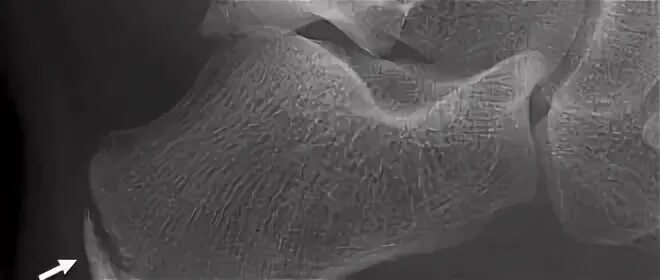

Болезнь шинца у детей код по мкб